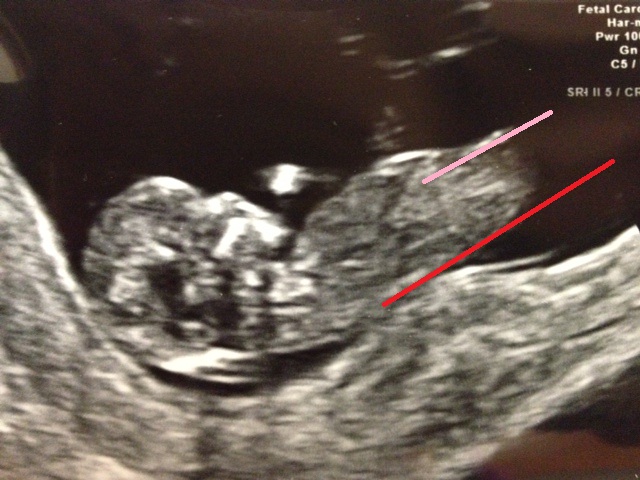

Hi everyone, here is a pic from my nt scan at 12w 2d today, tech said baby is measuring at 12w 4d!! I would really appreciate your gender guesses!!

This is how I see it:

Attachment 6244